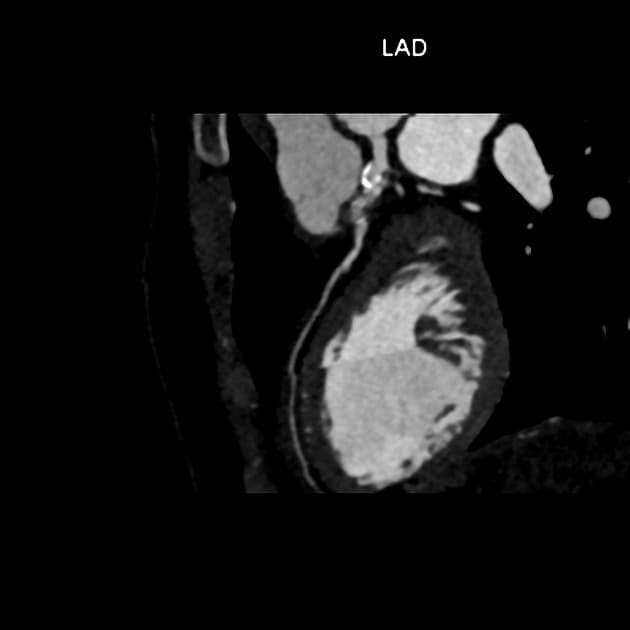

Ca bệnhPhình mạch vành khổng lồ trong bệnh Kawasaki

Phình mạch vành khổng lồ trong bệnh Kawasaki

- Phình mạch vành khổng lồ (giant coronary aneurysms) của động mạch vành phải (right coronary artery) và động mạch vành trước xuống (anterior descending coronary artery).

- Một phình mạch vành được coi là khổng lồ khi đường kính tuyệt đối > 8 mm hoặc có chỉ số z >10.

- Đường kính tối đa của đoạn gần động mạch vành phải là 16 mm, tham chiếu cho thấy lớn hơn động mạch chủ xuống (descending aorta).

- Nhận thấy hình khuyết thuốc (filling defect) trong lòng động mạch vành phải, nhiều khả năng do huyết khối (thrombus), tuy nhiên kích thước hình ảnh có thể lớn hơn thực tế do hiện tượng dòng chảy chậm (slow flow effect) – hiện tượng thường gặp trong huyết khối giả ở tiểu nhĩ (pseudo thrombus of atrial appendages). Việc chụp muộn (late acquisition) thường hữu ích để xác nhận sự hiện diện thực sự của huyết khối.

Phình mạch vành khổng lồ trong bệnh Kawasaki (Giant coronary aneurysms in Kawasaki disease)